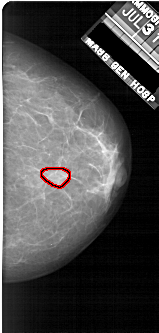

FILE: A_1922_1.RIGHT_MLO.OVERLAY

TOTAL_ABNORMALITIES 1

ABNORMALITY 1

LESION_TYPE MASS SHAPE OVAL MARGINS OBSCURED

ASSESSMENT 3

SUBTLETY 4

PATHOLOGY BENIGN

TOTAL_OUTLINES 1

BOUNDARY